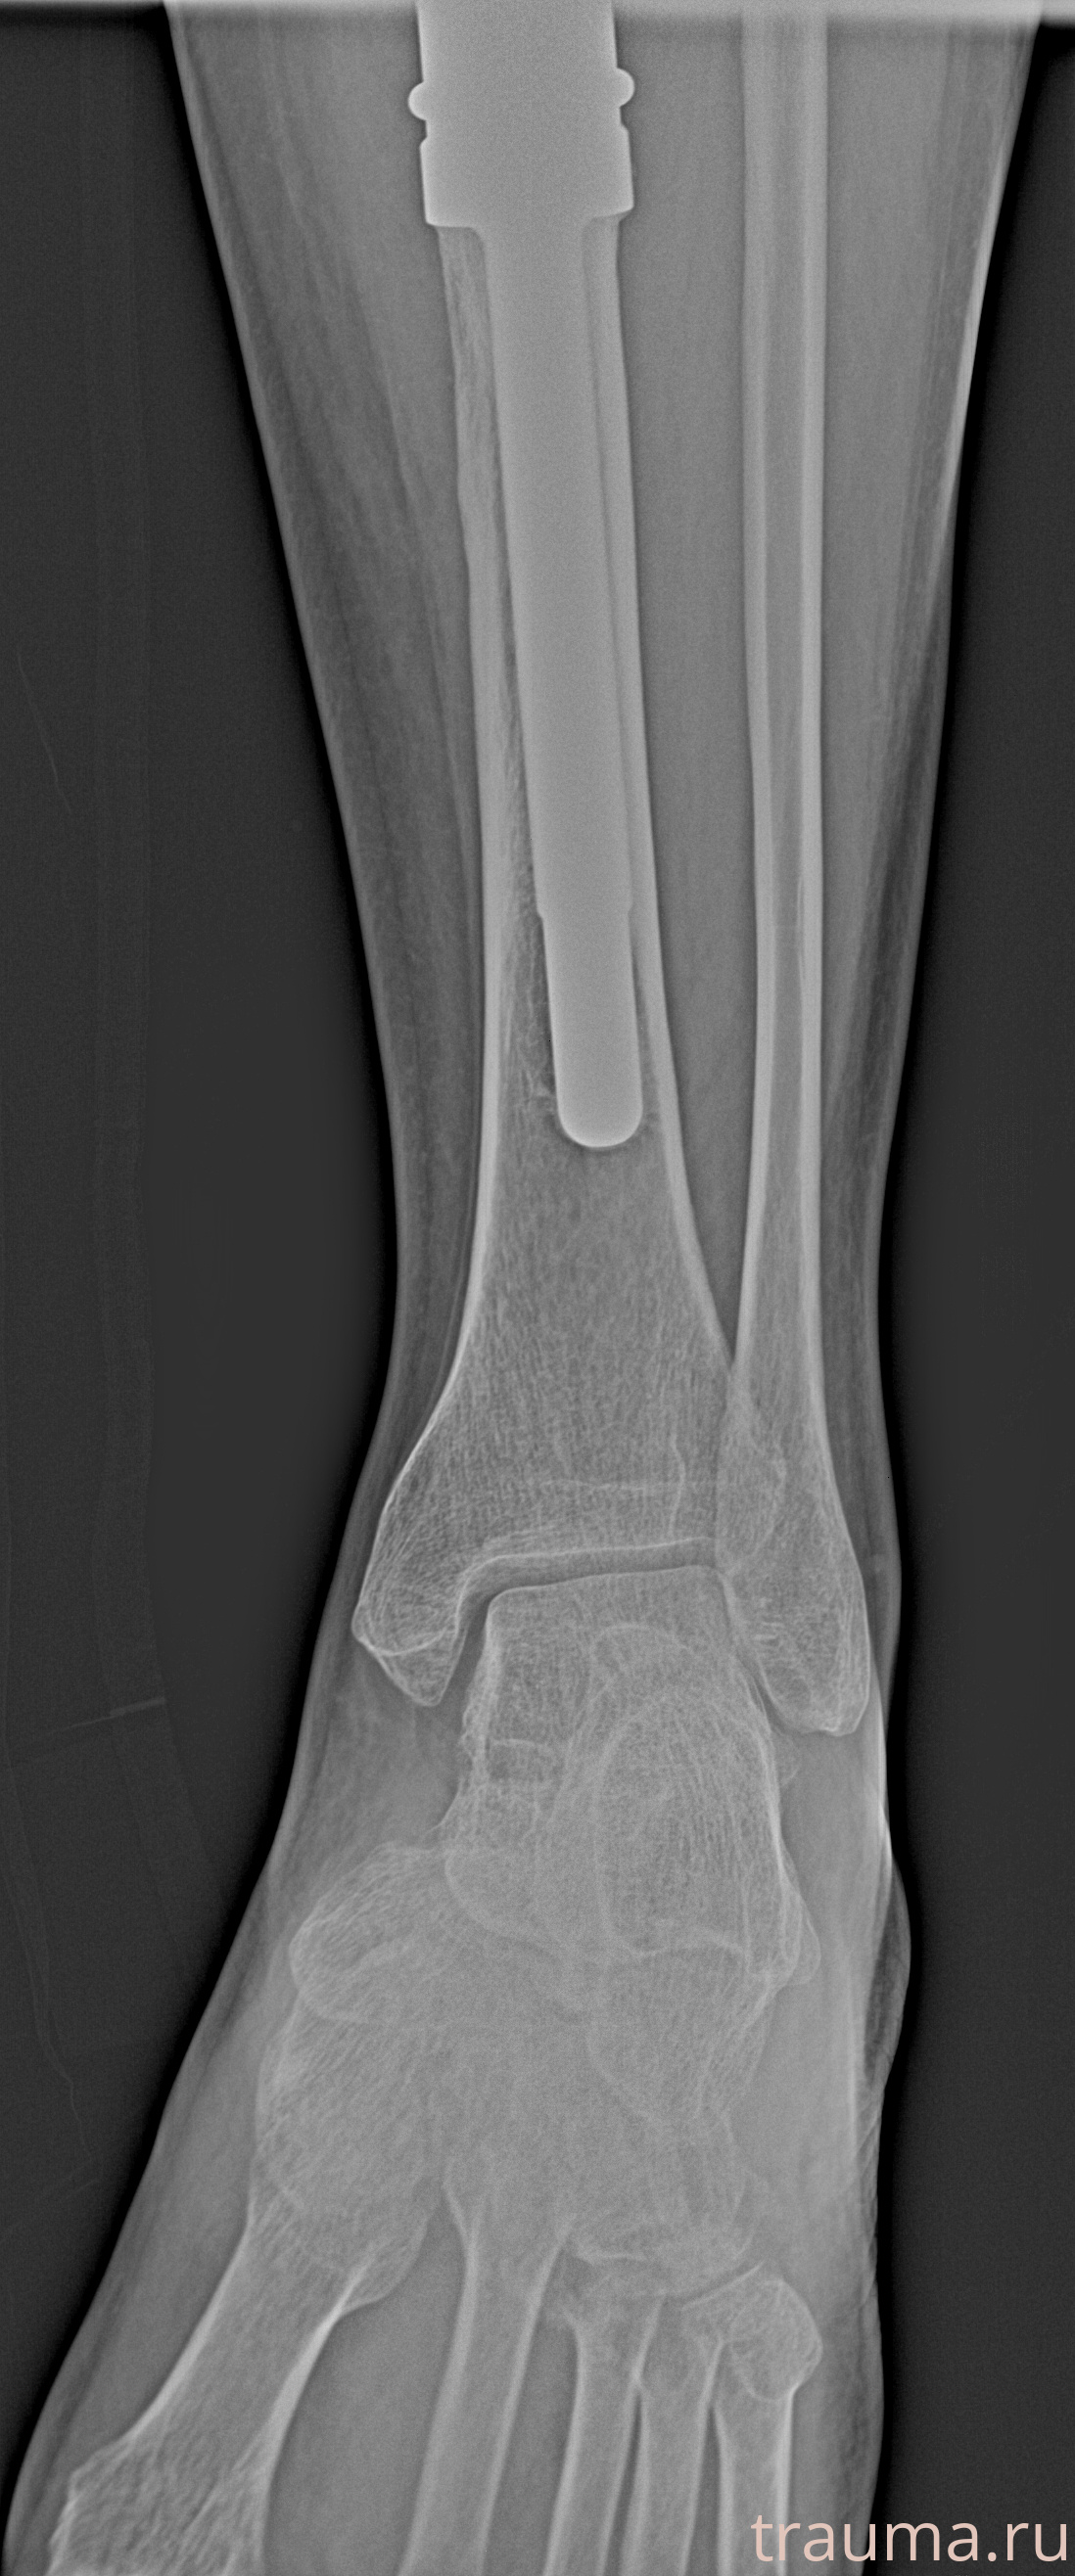

Рентгенограммы

Рентген на дому: по вашему адресу приезжает врач-рентгенолог, травматолог-ортопед с мобильным рентгеновским аппаратом, проводит диагностику травмы или заболевания, делает необходимые рентгенограммы, дает рекомендации по дальнейшему лечению. Получить качественные снимки в домашних условиях возможно благодаря уникальной методике, разработанной МосРентген Центром для института  Склифосовского